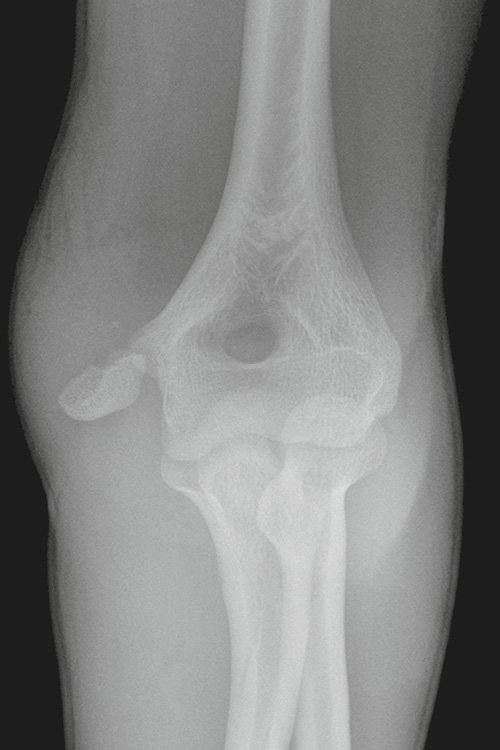

Little League elbow

• avulsion frature of the medial epicondyle